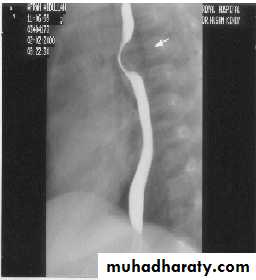

Filling defect

Types Causes Specific TypeIntra-luminal

Types Causes Specific TypeIntra-mural

Types Causes Specific TypeExtra-luminal

Types Causes Specific TypeSpecific type